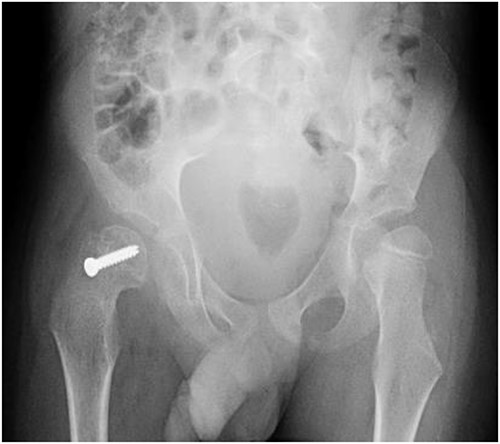

A 5-year-old independent ambulatory Middle Eastern boy with CP who was born preterm and developed grade III intraventricular haemorrhage and periventricular leucomalacia and was on AEDs, including valproic acid (VPA) and levetiracetam (LEV), for >3 years and was controlled over the last year (no history of seizure attack) presented to the emergency room (ER) with right hip pain and inability to bear weight for 4 weeks; the patient had no history of fever or trauma. Physical examination shows a thin, the weight is 12 kg, the height is 101 cm, vital signs within the normal range, tenderness over the right hip, and external rotation of the right hip, with restricted hip mobility. A radiological study was performed ~3 months before the patient presented to the ER for follow-up examination of a left hip coxa valgus deformity with no apparent abnormalities in the right hip (Fig. 1). Initial imaging studies conducted in the ER showed an anterior–posterior view of the pelvic radiograph, revealing Klein’s line [13] not intersecting the capital femoral epiphysis (Fig. 2), and frog-leg lateral view radiograph of the right hip (Fig. 3) confirmed SCFE and Southwick’s slip angle [13] of ~50° (moderate). Laboratory findings were clear for endocrine and renal diseases or infection, except for low vitamin D (total 25-OH Vitamin D: 43.4 nmol/L), suggesting vitamin D insufficiency. The diagnosis was confirmed with clinical and radiological studies as right-sided unstable SCFE requiring surgery. Surgical intervention was performed with percutaneous in situ fixation using a single fully threaded 4.5-mm cannulated screw (Fig. 4). Postsurgical rehabilitation included non-weight-bearing right lower extremities for 6 weeks. Regular follow-up with serial radiology studies showed stable fixation with no migration of screw or further slippage at 6 weeks (Fig. 5) and 3 (Fig. 6), 15 (Fig. 7), and 36 months (Fig. 8). During follow-up, a painless range of motion in the right hip was observed, with full weight-bearing and resumption of his usual activities with no complaints.

Pelvic anterior–posterior radiograph showing coxa valga deformity in the left hip.